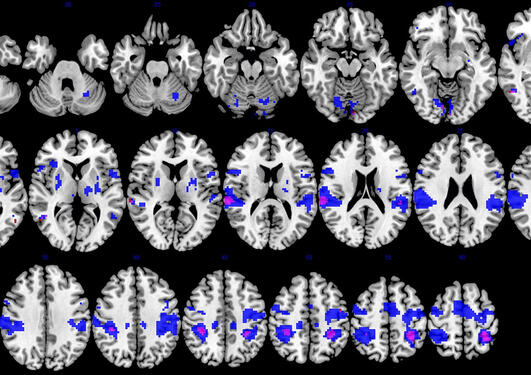

In this study longitudinal changes in neuronal activity in a group of patients with subacute stroke were examined when observing and executing a bimanual movement task. The results suggest that plastic changes also occur in potential mirror neurons